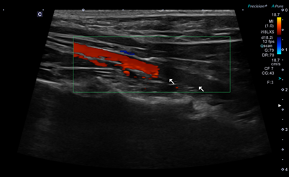

좌심방이 혈류 속도 측정 결과

- Filling velocity: 16.1 cm/s

- Emptying velocity: 16.8 cm/s (정상 ≤28 cm/s)

→ 혈액이 좌심방이에 오래 머무르는 뚜렷한 혈류 저하가 확인되었습니다.

환자의 심장초음파 사진(좌심이 혈류 속도 filling velocity 16.1cm/s, emptying 16.8cm/s 두드러진 감소 (정상 28cm/s 이내)) / 출처: 24시 동탄리더스동물의료원